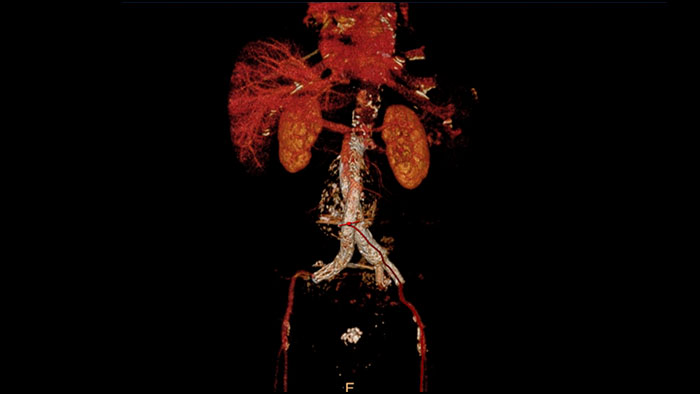

The application is designed to examine and quantify different types of vascular lesions from CT and MR, providing modes of inspection, labeling of different vascular lesions, and customizable volume rendering.

Take advantage of a comprehensive set of multi-modality advanced visualization vascular applications to examine and quantify vascular lesions. Accelerate workflows with customized views, and enhance workflows for specific findings creation.

Contrast arterial structures with surrounding bone and soft tissue to assist in identification of vascular abnormalities